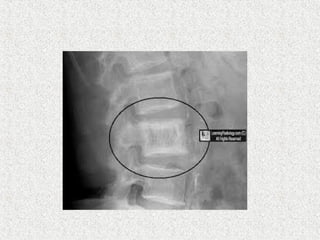

 Spine

 Picture frame sign

 Ivory vertebra

 Squaring on lateral view

 Vertical trabecular thickening